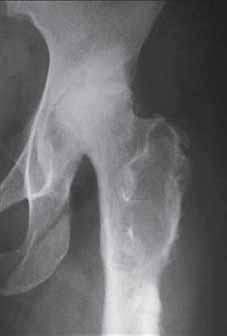

b

Rycina 14.2. Osteokondukcyjne pobudzenie zrostu kostnego belką i przeszczepami kości allogenicznej złamania okołoprotezowego kości udowej lewej po realoplastyce rewizyjnej stawu kolanowego; a) rentgenogram w projekcji przednio-tylnej (a-p), b) rentgenogram w projekcji bocznej (l).